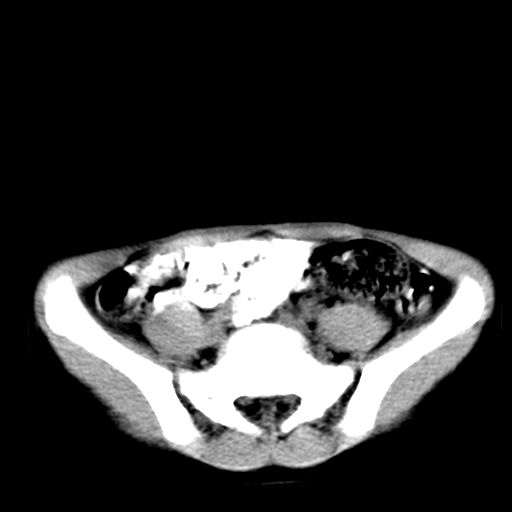

腹部好象未见异常。

腹部ct平扫未见明确异常

腹部ct平扫不能提示哪里有病变。